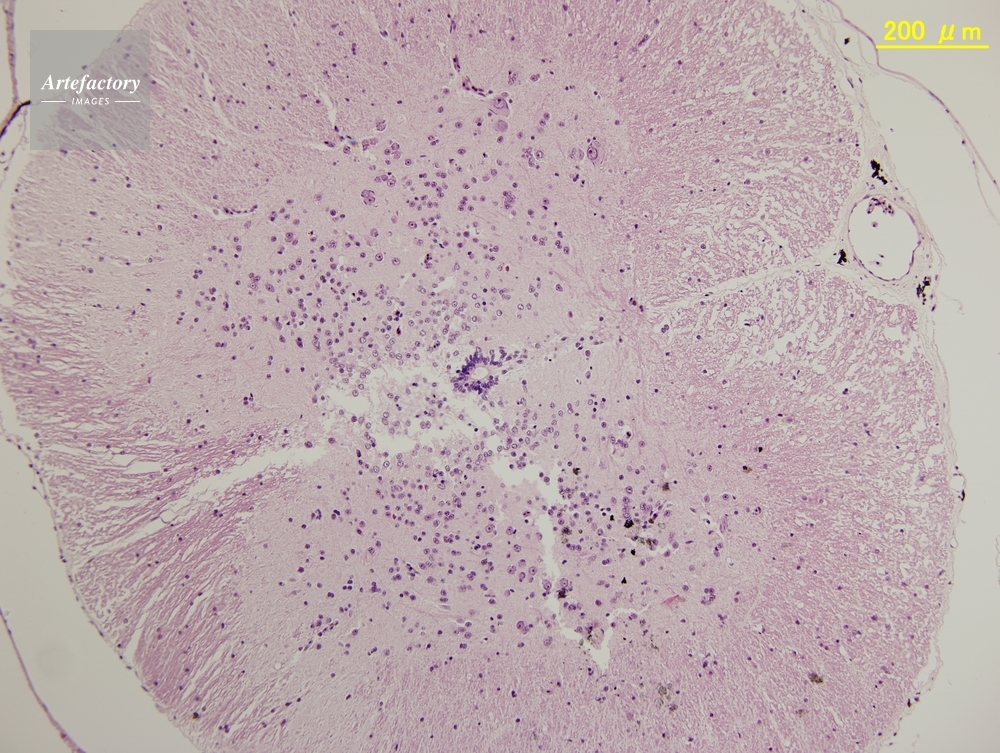

| 作品タイトル | ウシガエル,脊髄 | モデルリリース | なし | |

| 作家 | OLYMPUS CORPORATION Technolab | プロパティリリース | なし | |